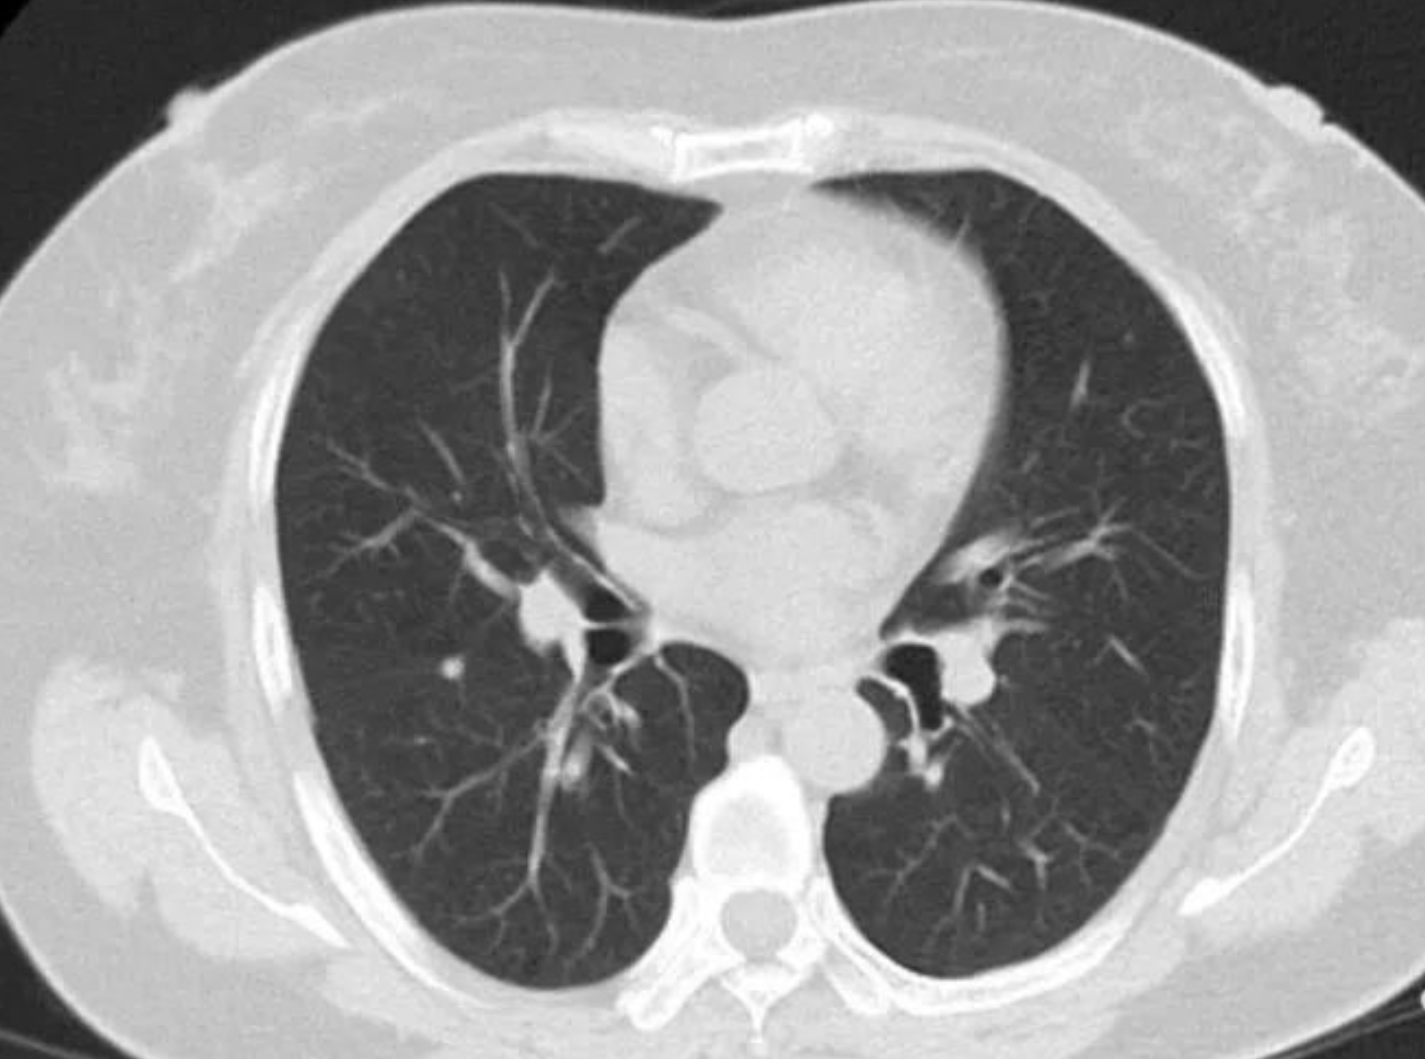

肺结节,是指肺内直径小于或等于3厘米的类圆形或不规则形病灶。为什么不少人“阳康”后,查CT查出了肺结节呢?

在此提醒,通过胸部CT发现的肺结节中,92%以上的肺结节是良性结节。特别是对于初次发现的肺小结节(直径<1cm),首次发现时不需过度焦虑、着急进行手术治疗。

临床医生会根据CT影像特征及临床特征(如年龄、既往肿瘤病史、吸烟史、职业史)综合分析后,对于低危/中危患者建议定期随访复查CT,进行动态对比前后改变再做出良恶性判断。

低危/中危的肺结节:可间隔12个月、6个月、3个月后复查低剂量螺旋CT,并且与上一次的CT结果进行前后对比:观察肺结节有没有增大?密度有没有增高?有没有出现特征性的影像学表现?

需要特别关注磨玻璃结节

如果在连续的CT随访观察中都能监测到,并且在1年~2年内都变化不大,就要高度怀疑这个磨玻璃结节是早期肺癌。但也不用太紧张,这一类型的肺癌早期发展是非常缓慢的,有充分的时间对结节进行观察,不用急于手术治疗。

相反,如果发现磨玻璃结节在随访复查的CT中短期内出现了明显的变化,比如增长得特别快,或明显缩小甚至消失,或位置、形态发生改变,那这个结节是良性的可能性就大。